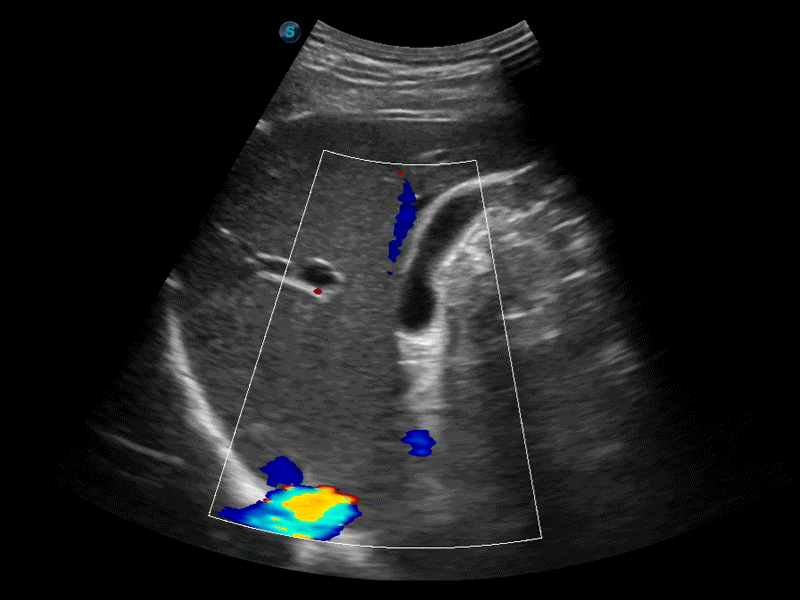

高分辨率血流成像技術(shù)提高了對低速血流信號的檢測能力。在提高空間分辨率的同時,也克服了血流外溢現(xiàn)象,為用戶提供更加真實的血流動力學(xué)信息。

凸陣、線陣和相控陣探頭進(jìn)行實時掃描時,開啟擴(kuò)展成像模式,可以擴(kuò)展超聲圖像視野,以便更完整地查看大的病灶或組織器官的解剖結(jié)構(gòu)。

通過色彩血流和實時寬景相結(jié)合,可觀察到完整的靜脈或動脈的血流,方便醫(yī)生檢查。實時掃查過程中,如有任何操作失誤也可以很容易地進(jìn)行回掃擦除,而不會中斷掃查。